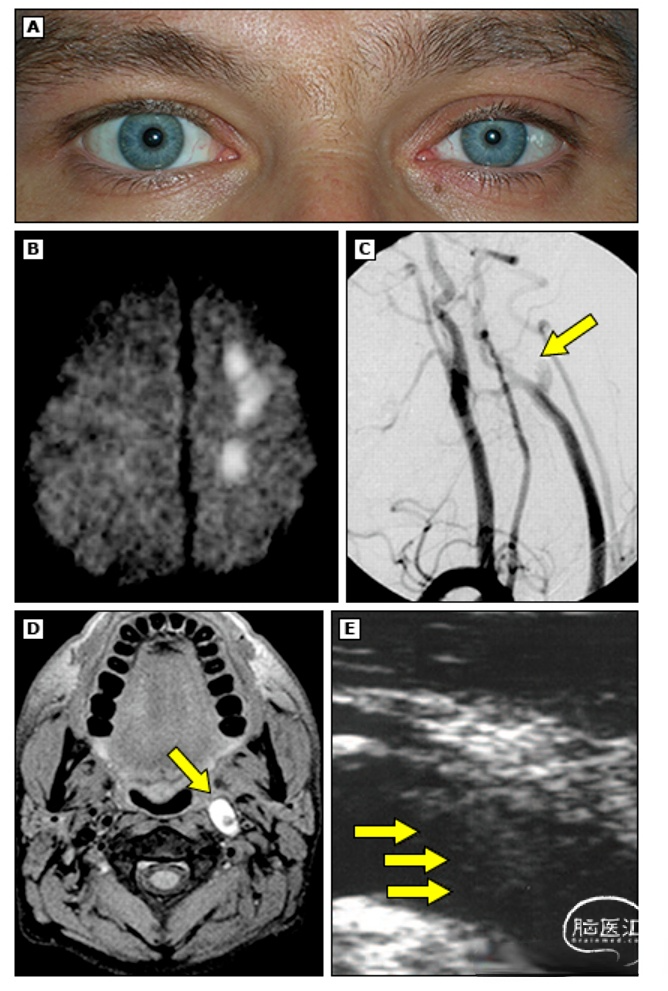

单纯性眼眶或单眼疼痛是颈动脉夹层的一种罕见表现。Horner综合征 — 大约25%的颈动脉夹层患者存在Horner综合征。

最常由跨过颈内动脉外表面的交感神经纤维扩张导致。在颈内动脉夹层患者中,Horner综合征通常是部分性的,包括上睑下垂和瞳孔缩小,但不出现无汗症。这是因为支配面部出汗和血管扩张的交感神经纤维是在颈上神经节处从眼交感神经通路中分出,并伴行于颈外动脉。

颅神经或颈神经病变 — 颈动脉夹层可在高达12%的患者中造成单处或多处压迫性颅神经病变。颅神经Ⅻ最常受累,其次是颅神经Ⅸ;颅神经Ⅲ、Ⅴ和Ⅵ受累较为少见。颈神经根受累是椎动脉夹层的一个罕见并发症。

我们会采用头部MRI联合头颈部磁共振血管造影(magnetic resonance angiography, MRA),或者头部CT联合头颈部CT血管造影(computed tomography angiography, CTA)进行紧急的无创多模式影像学检查,以验证头颈部动脉夹层的初始诊断,并指导连续的治疗决策。虽然临床特征可能提示夹层,但诊断仍需要神经影像学表现来证实,尤其是显示存在狭长的锥形动脉狭窄、锥形闭塞、夹层动脉瘤(假性动脉瘤)、内膜瓣、双腔或壁内血肿。

典型的影像学表现

动脉夹层的血管造影表现包括:

●线状征

●锥形狭窄、锥形闭塞或火焰样闭塞

●内膜瓣

●夹层动脉瘤

●壁内血肿–新月征

●远端呈囊状

一项纳入48例颈动脉夹层连续患者的人群研究显示,诊断性神经影像学模式为狭长锥形狭窄、锥形闭塞和夹层动脉瘤的患者比例分别为48%、35%和17%。一项有关自发性椎动脉夹层患者的欧洲前瞻性研究显示,MRI中最常见的诊断性神经影像学表现是壁内血肿,在157例椎动脉夹层患者中多达91%。

在MRI检查中,壁内血肿特有的新月征表现为一种偏心的高信号环围绕一个低信号的动脉腔。这种新月征传统上见于T1加权脂肪饱和MRI序列,但也可能见于其他序列(如,弥散加权成像)或CTA。壁内血肿的MRI高信号程度以及高铁血红蛋白含量随病变的持续时间而变化。椎动脉水平段的夹层可能难以诊断,这是因为由于血管的走向,典型的新月征可能缺失,而且椎静脉丛也可能呈高信号表现。椎动脉的走行也可能限制对新月征的显像,因为管腔可能未闭塞,周围存在更不规则的“枕骨下外皮(suboccipital rind)”征。对多模式CT或MRI源图像进行评估是明确血管壁异常的关键。